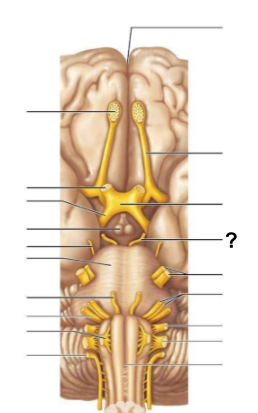

The __________ is responsible for processing olfactory (smell) signals before sending them deeper into the brain

Olfactory bulb

The __________ carries olfactory information from the olfactory bulb to the brain

Olfactory tract

The __________ connects the cerebrum to the spinal cord and contains centers that control heart rate and respiration

Medulla oblongata

The ____ is a rounded structure on the brain stem that relays signals between the cerebrum and the cerebellum

Pons

Cranial nerve (V), the __________ nerve, is responsible for facial sensation and motor control of chewing muscles

Trigeminal

Cranial nerve (VIII), also known as the __________ nerve, is responsible for hearing and balance

Vestibulocochlear

The __________ nerve (cranial nerve III) controls most of the eye’s movements, including pupil constriction

Oculomotor